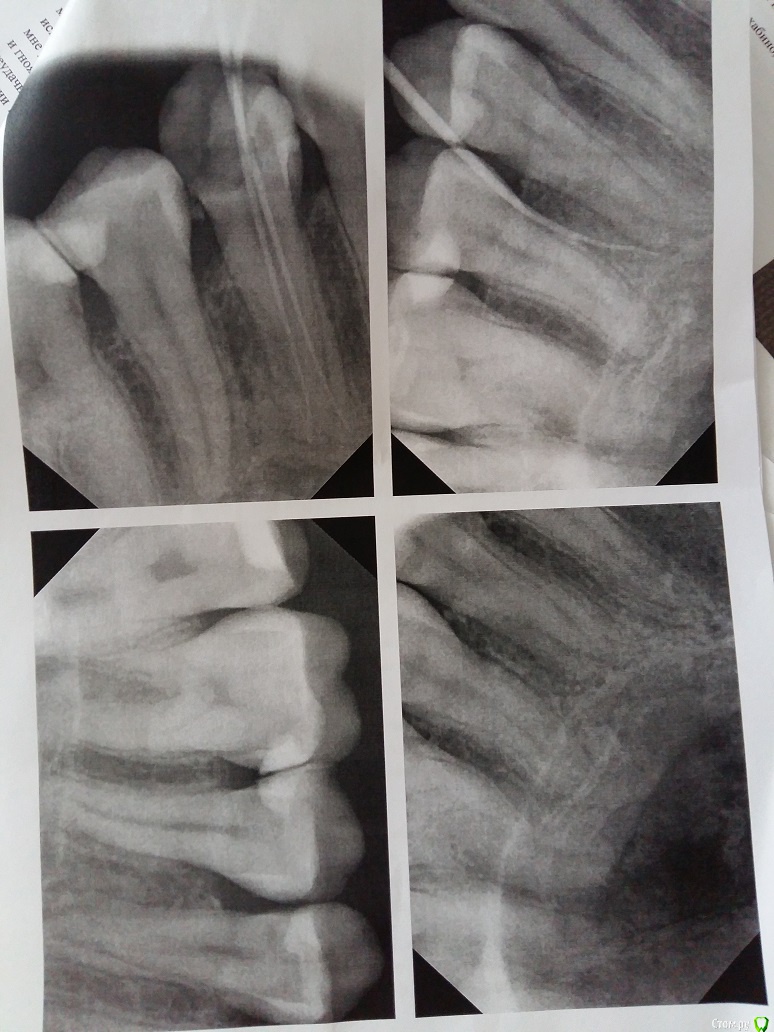

Kateklim Опубликовано 27 ноября, 2015 Автор Поделиться Опубликовано 27 ноября, 2015 Снимки, которые мне дали в частной клинике. Ссылка на комментарий

Гарриевич Опубликовано 27 ноября, 2015 Поделиться Опубликовано 27 ноября, 2015 по снимкам все адекватноесли использовали правильный протокол лечения, то результат будет хороший Ссылка на комментарий

IvanK Опубликовано 27 ноября, 2015 Поделиться Опубликовано 27 ноября, 2015 Хочу вернуть деньги в частной клинике. Думаю, что Вы торопитесь Лечение таких процессов почти везде без гарантии 2 Ссылка на комментарий